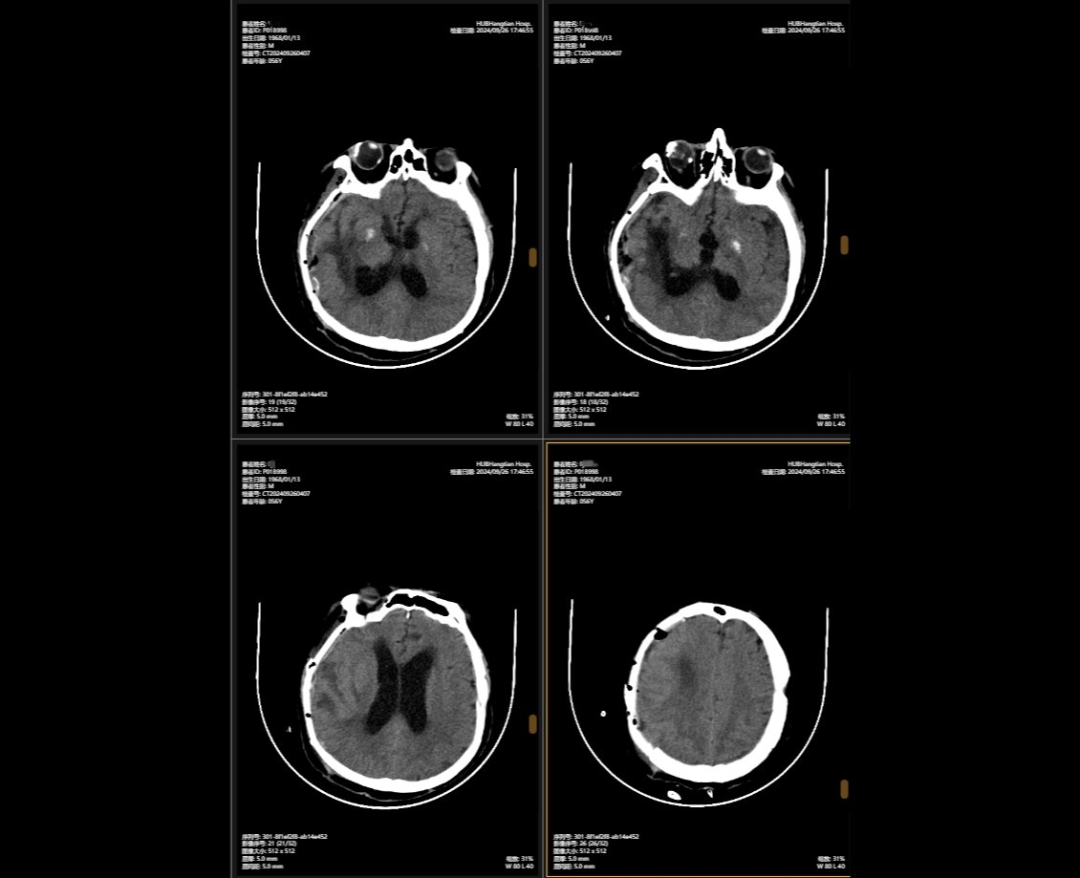

2024年5月,56歲的李先生(化名)不幸遭遇嚴重車禍,當場昏迷,生命垂危。他被緊急送往湖北航天醫(yī)院后,檢查結(jié)果讓所有人心頭一緊:他的頭部受到嚴重撞擊,不僅有多處出血,腦組織也有挫傷,甚至連呼吸心跳的“總司令部”——腦干都受了傷。除此之外,還有顱骨、頸椎和多處肋骨骨折,情況萬分危急。

李先生頭部的多處損傷就像一顆顆“炸彈”,隨時可能危及生命。航醫(yī)神經(jīng)外科團隊接診后,面對如此復雜的顱內(nèi)損傷,神經(jīng)外科主任陳義勇當機立斷,一方面做好周密的手術(shù)準備,一方面迅速展開多學科會診,多學科團隊緊急集合,反復協(xié)商探討,一同制定了詳盡手術(shù)方案。手術(shù)方案確認后,神外團隊爭分奪秒,第一時間為李先生實施了顱內(nèi)多發(fā)血腫清除術(shù)+右側(cè)開顱顱內(nèi)減壓+去骨瓣減壓術(shù)+左側(cè)硬膜外血腫清除術(shù)+矢狀竇破裂止血術(shù)。手術(shù)過程中,醫(yī)生們精準操作,成功止住了出血,最大限度地保護了正常腦組織,為李先生贏得了生的希望。

顱骨缺損修補術(shù)前術(shù)后對比